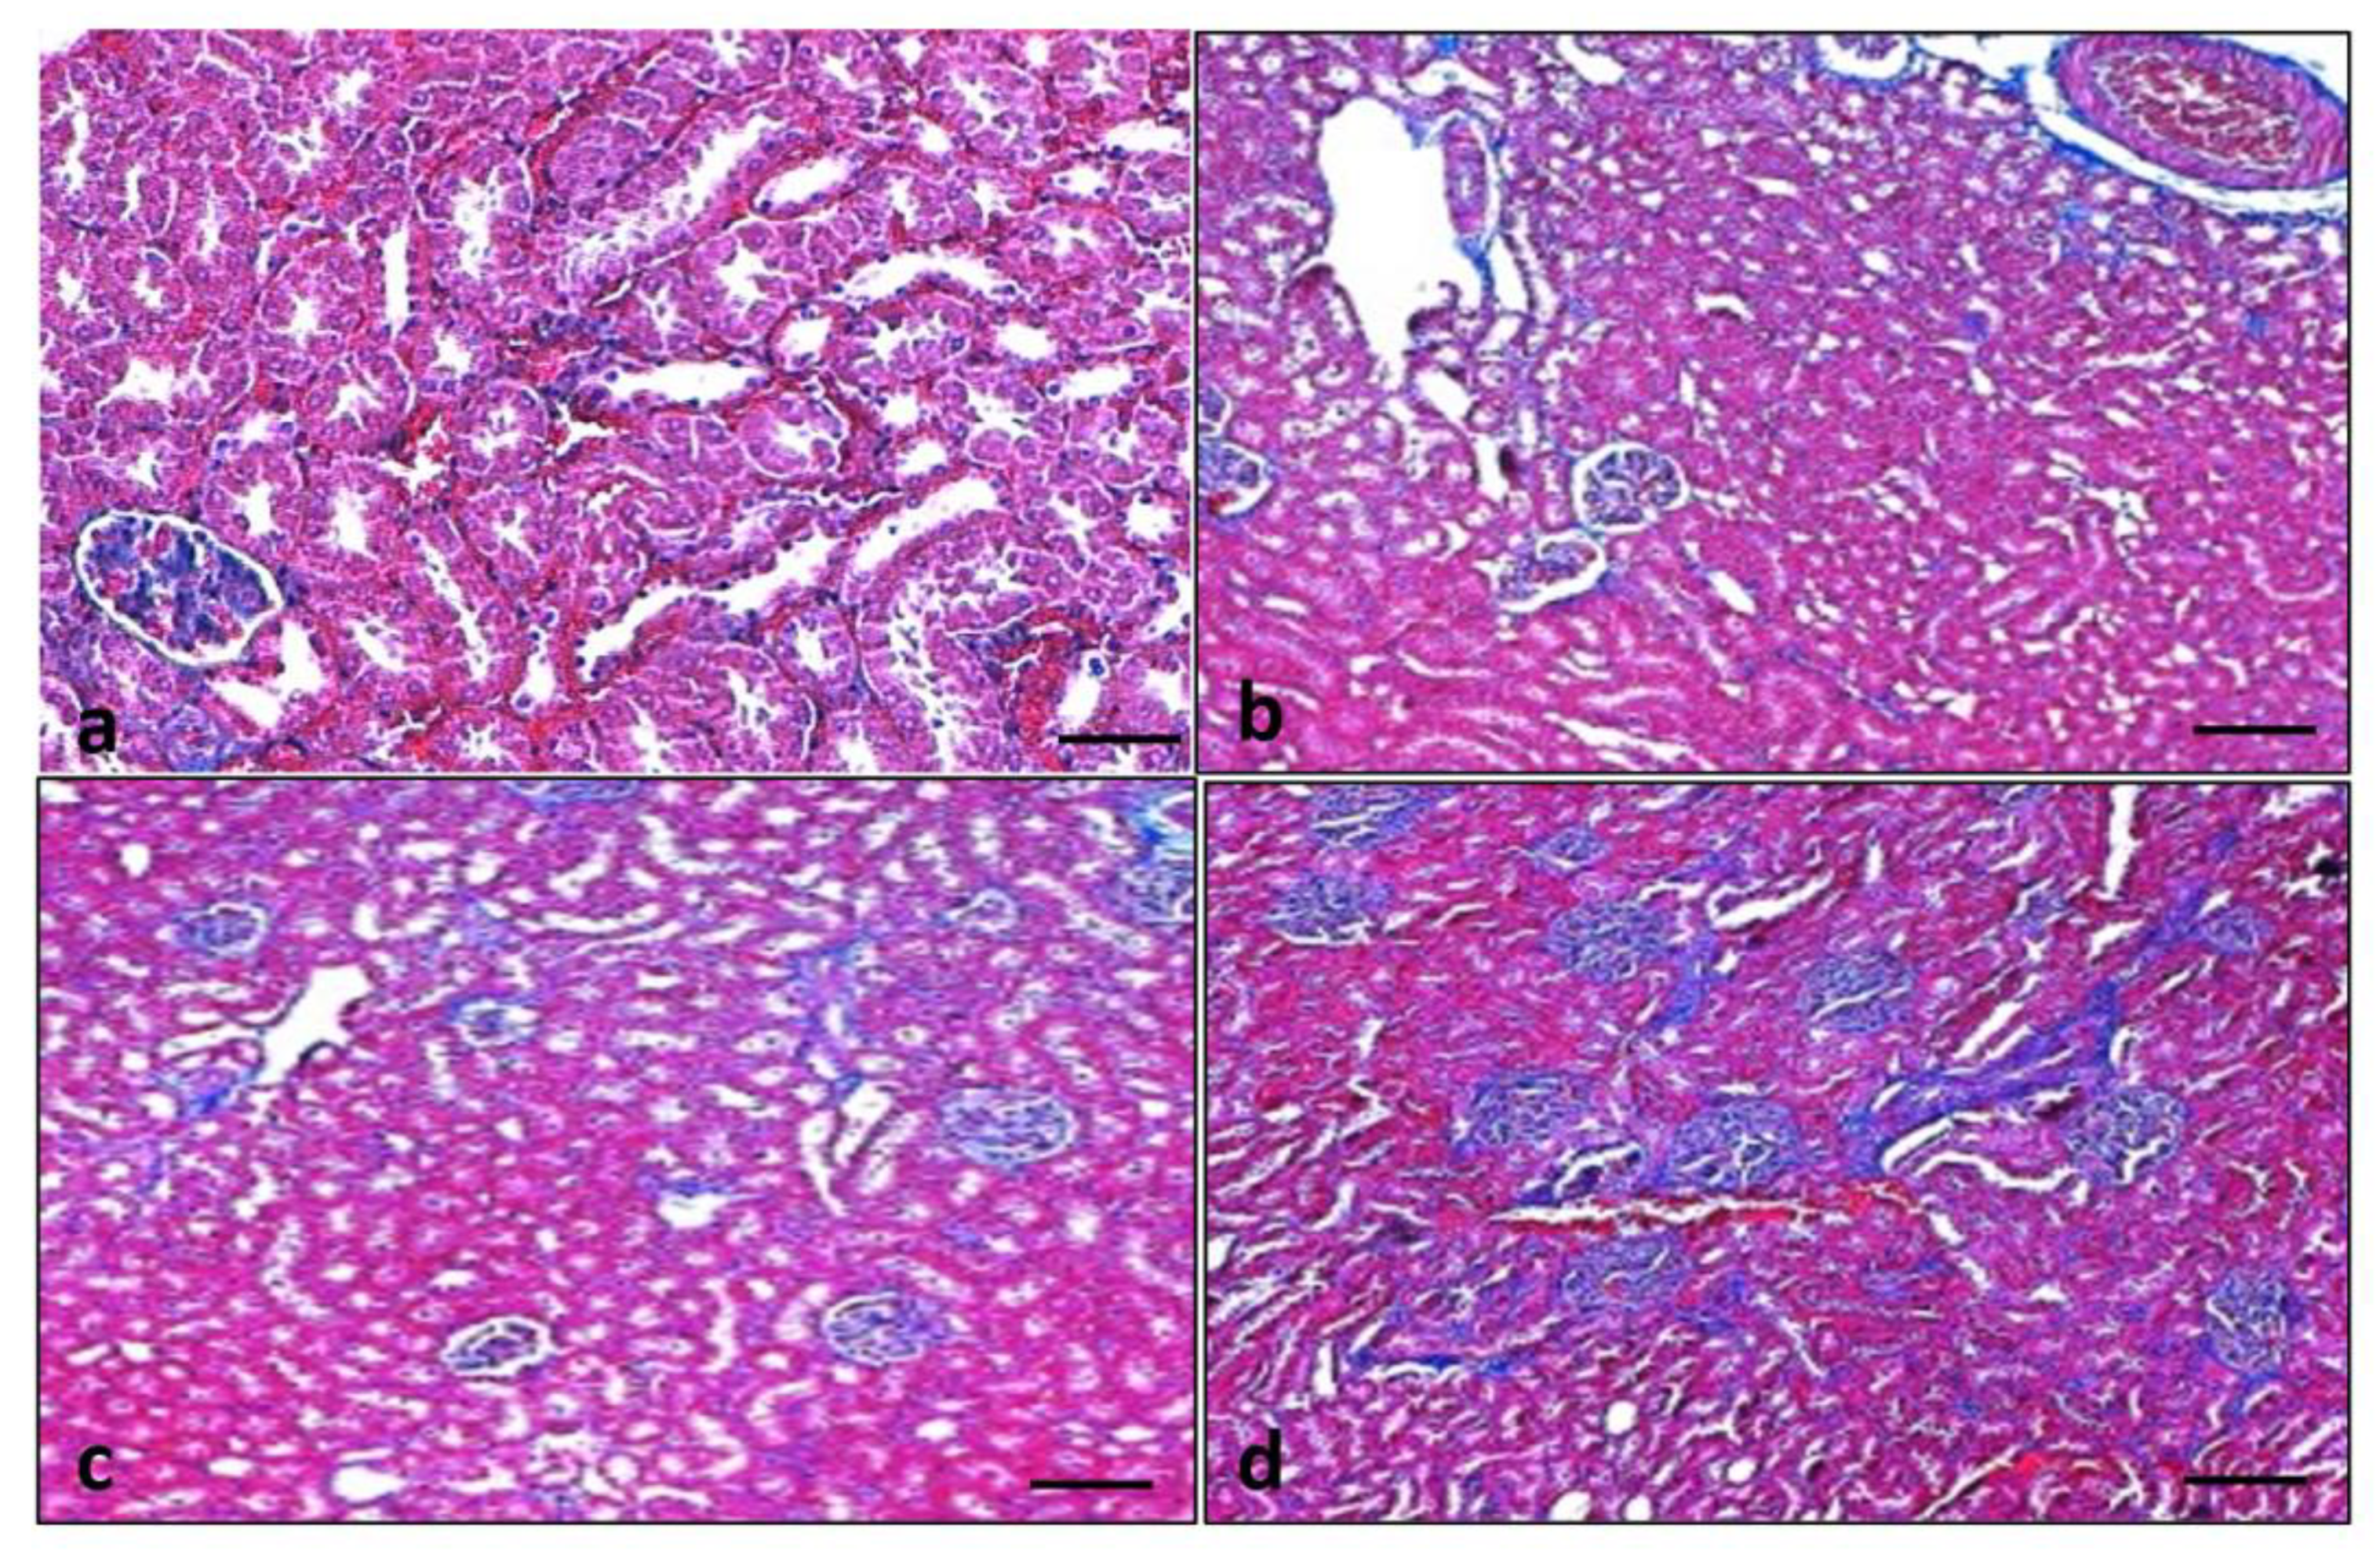

3.10. Effect of Quercetin on Renal Fibrosis

3.11. Effect of Quercetin on Renal Fibrosis of STZ-Induced Diabetic Rats